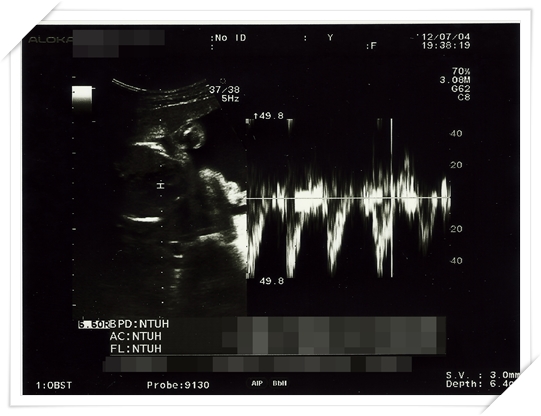

好期待可以看看超音波 更期待可以拿到最新的照片

而且事實證明 小鴨也真的長得比較快

都拜高蛋白所賜啦~~~~

他的“三圍” 可是越來越 “傲人” 了呢 哈哈哈哈哈!!

(這裡的三圍指的是 頭圍 大腿骨長度 以及身長 別想歪阿~~~)